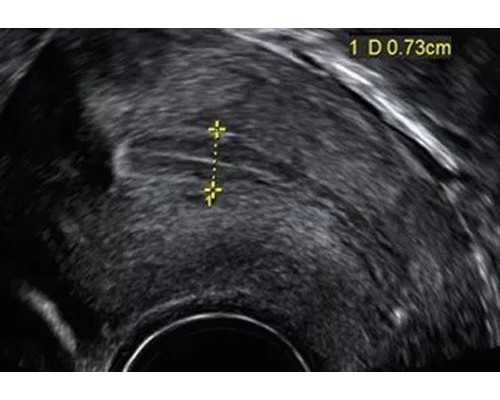

宫颈息肉影响怀孕吗

您好,根据您描述的情况考虑,如果宫颈息肉偏小,且没有感染症状,正常不会影响怀孕;如果宫颈息肉偏大,且堵塞宫颈口,这时候会对怀孕产生影响。所以需要通过手术摘除宫颈息肉,并且进行病理组织检查,如果结果是良性的,那就可以正常怀孕。希望该建议可以帮助到您,祝您健康。